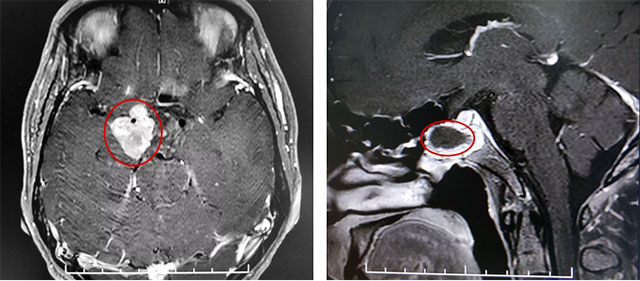

患者蔡先生(化名)因持续头痛、视力下降被查出是垂体无功能巨大腺瘤,肿瘤大小超过3cm。在杭州一家医院做了经蝶窦垂体瘤切除手术后,由于术后肿瘤残余较多,出现头痛情况,视力较术前未见明显改观,左侧视力0.12,右侧视力0.1。后慕名来到上海蓝十字脑科医院。

李士其教授指出,经鼻蝶手术主要用于肿瘤位于鞍内者,对于鞍内、鞍上均有生长的巨大垂体瘤,考虑联合入路手术,部分患者也可以考虑多次经鼻蝶手术。

该巨大垂体腺瘤患者鞍上区域残余肿瘤偏向右侧,只能通过开颅手术切除。

在充分准备并征得家属同意后,李士其教授在吴治群博士、黄秀夫医生协助下为患者行开颅手术,经翼点入路将残余约2.5cm*2cm*2cm大小肿瘤切除。